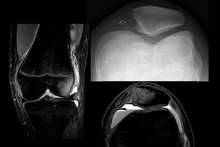

Diagnosis

To assess the knee, a clinician can perform the patellar apprehension test by moving the patella back and forth while the patient flexes the knee at approximately 30 degrees.[6]

The patient can do the patella tracking assessment by making a single leg squat and standing, or by lying on his or her back with knee extended from flexed position. A patella that slips medially on early flexion is called the J sign, and indicates imbalance between the VMO and lateral structures.[14]